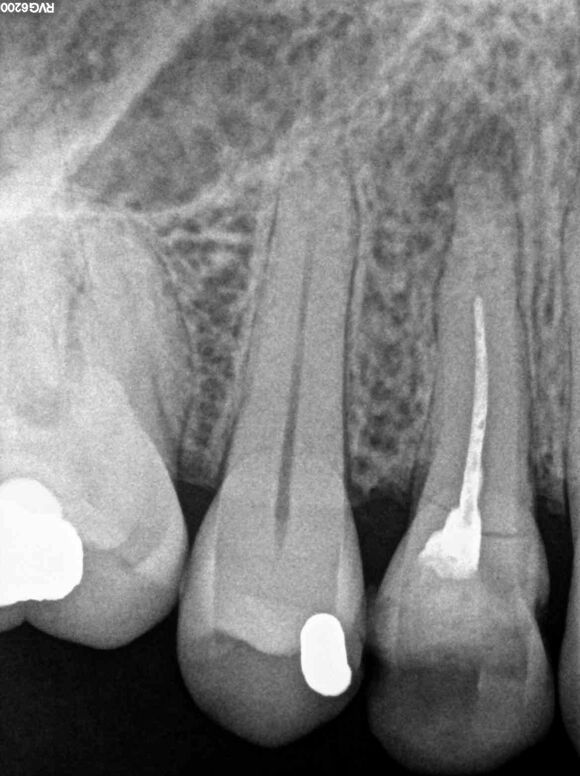

Beispiel 3: Vorher

Unvollständige Wurzelfüllung mit anhaltenden Beschwerden.

Beispiel 3: Nachher

Verlängert, vervollständigt und Beschwerdefreiheit.